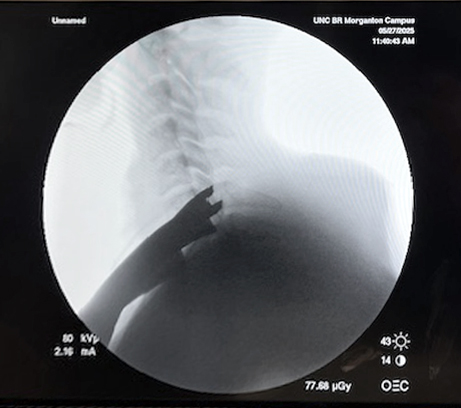

Visualization | Lower Cervical Spine Procedures

Achieve Better Visualization, Especially in Higher BMI patients.